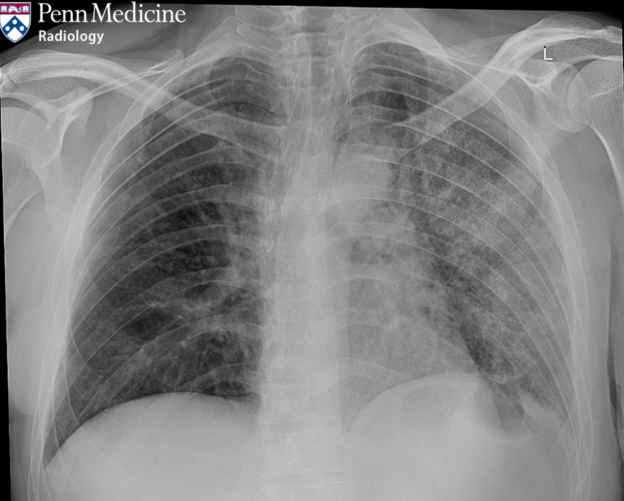

38-year-old man with six-week history of persistent cough

A 38-year-old man with no known medical history presented to the emergency department for a six-week history of persistent cough.